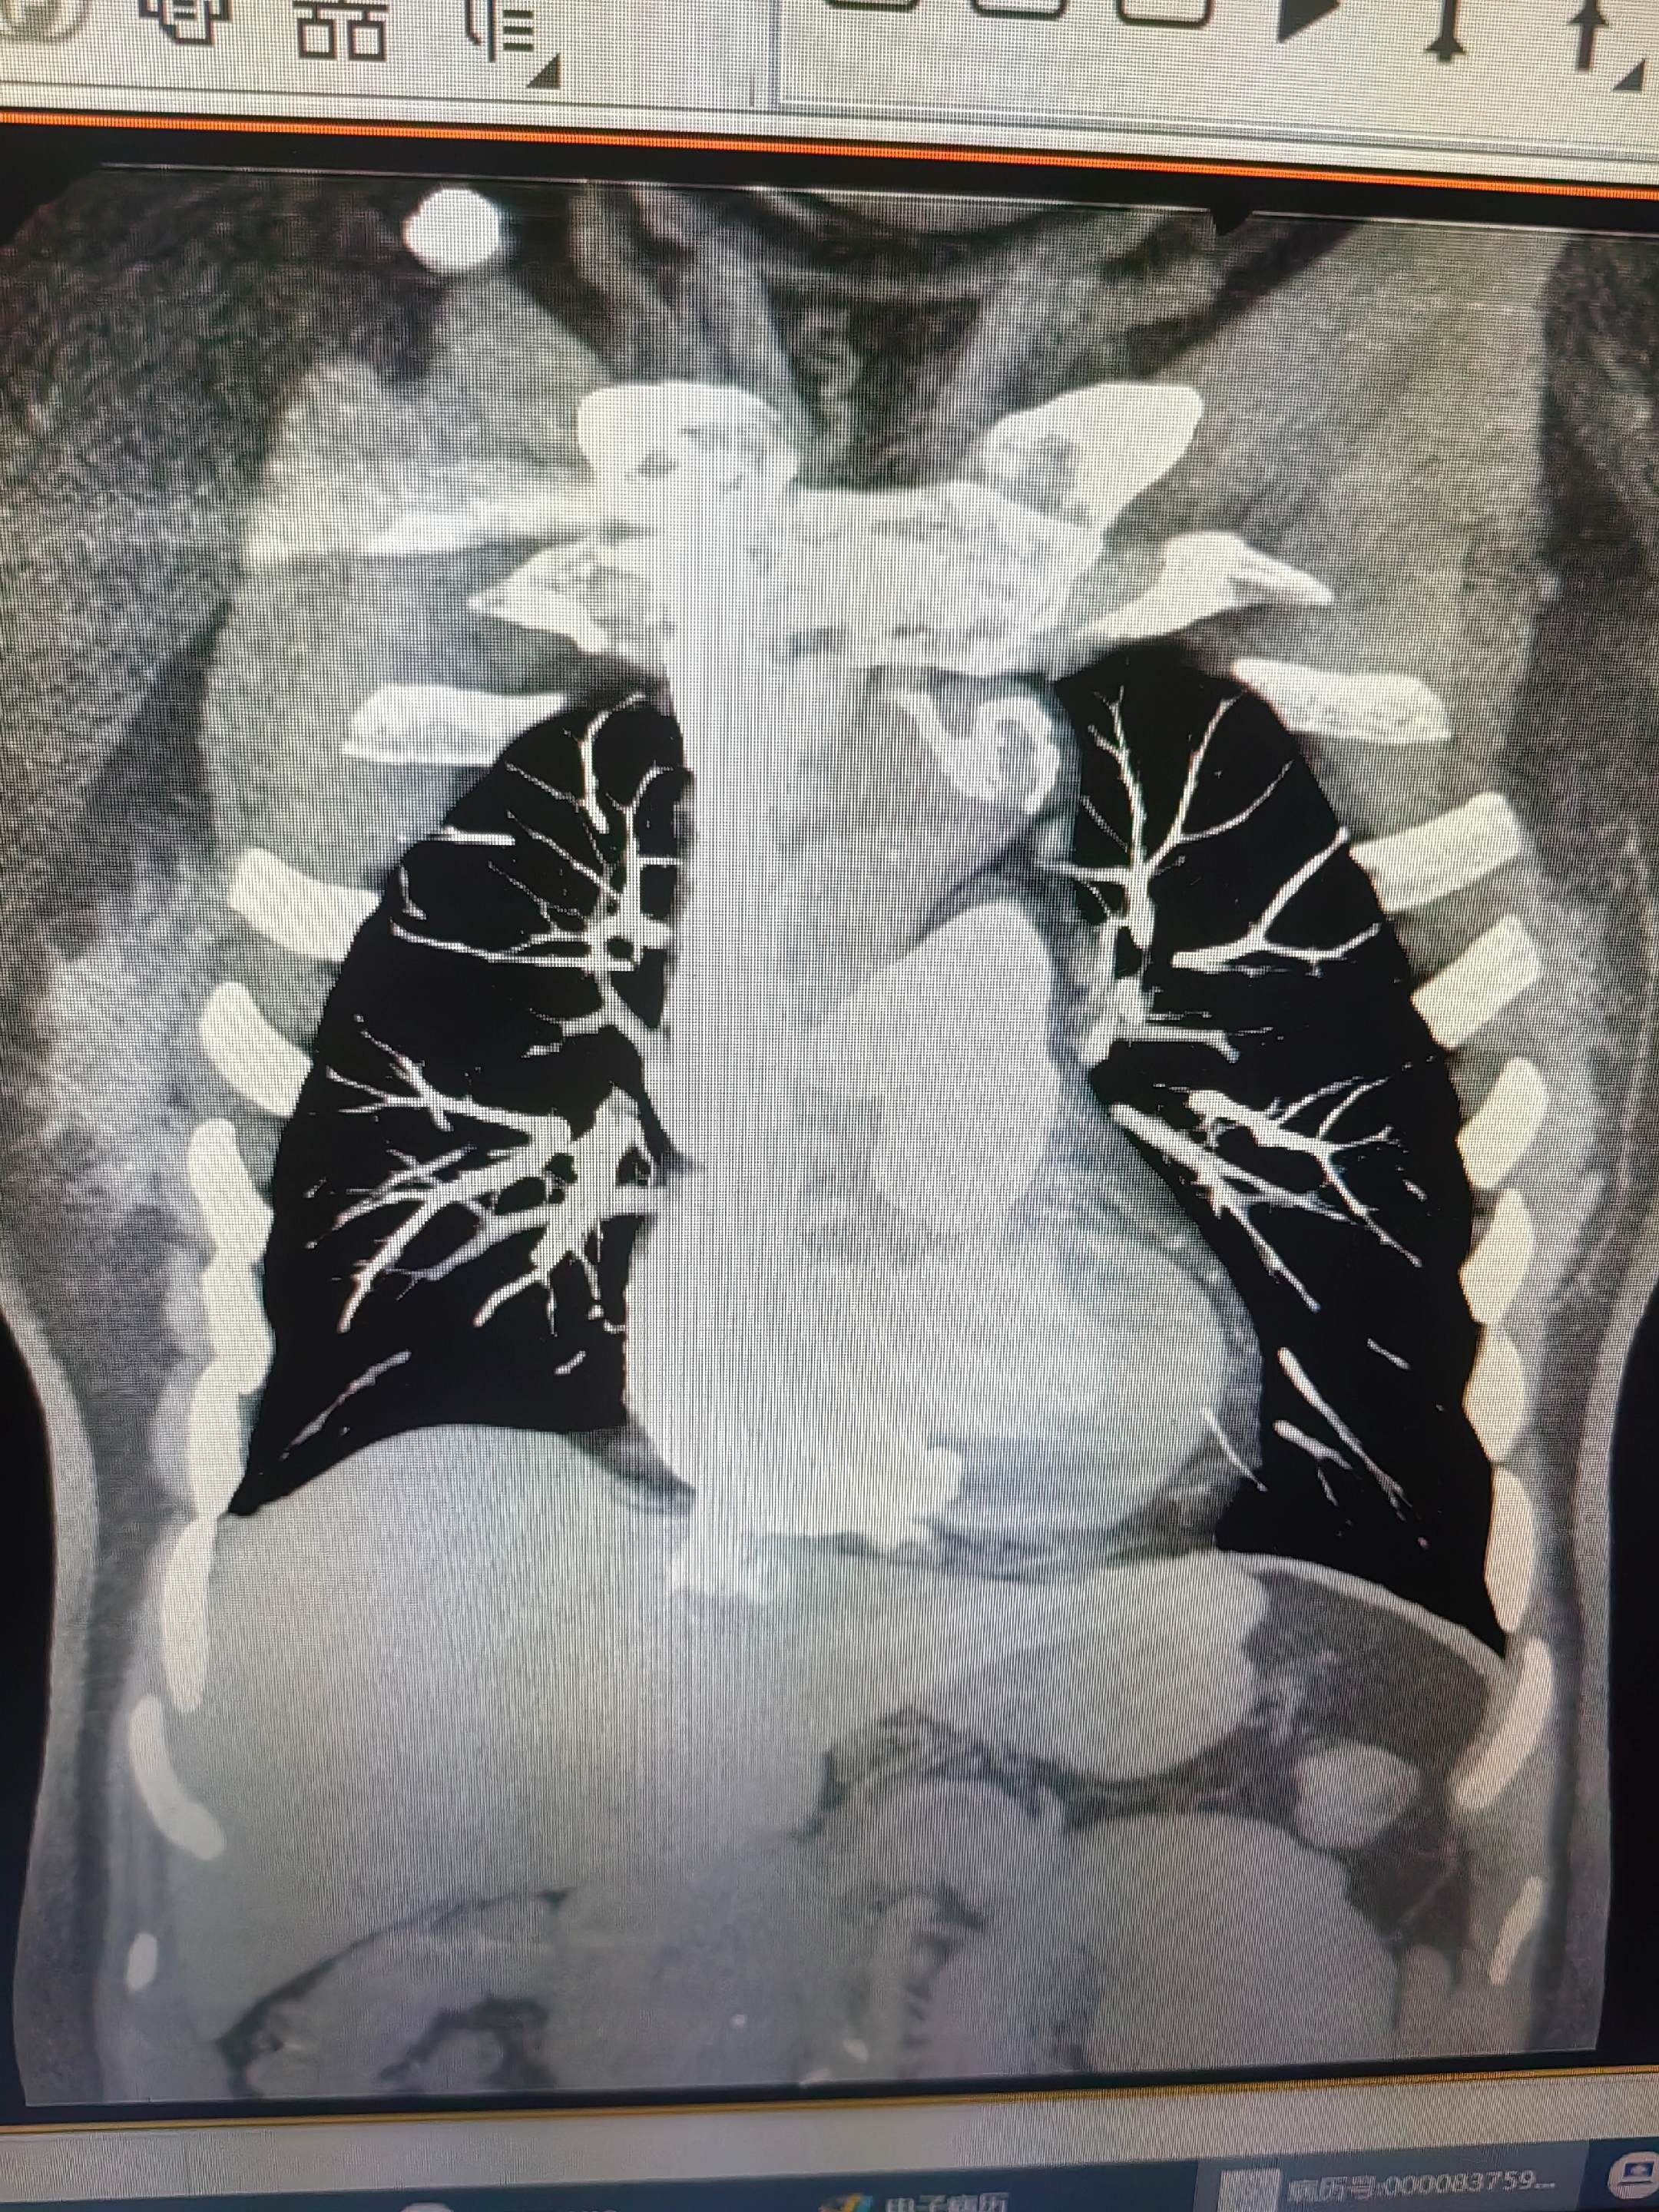

肺栓塞。